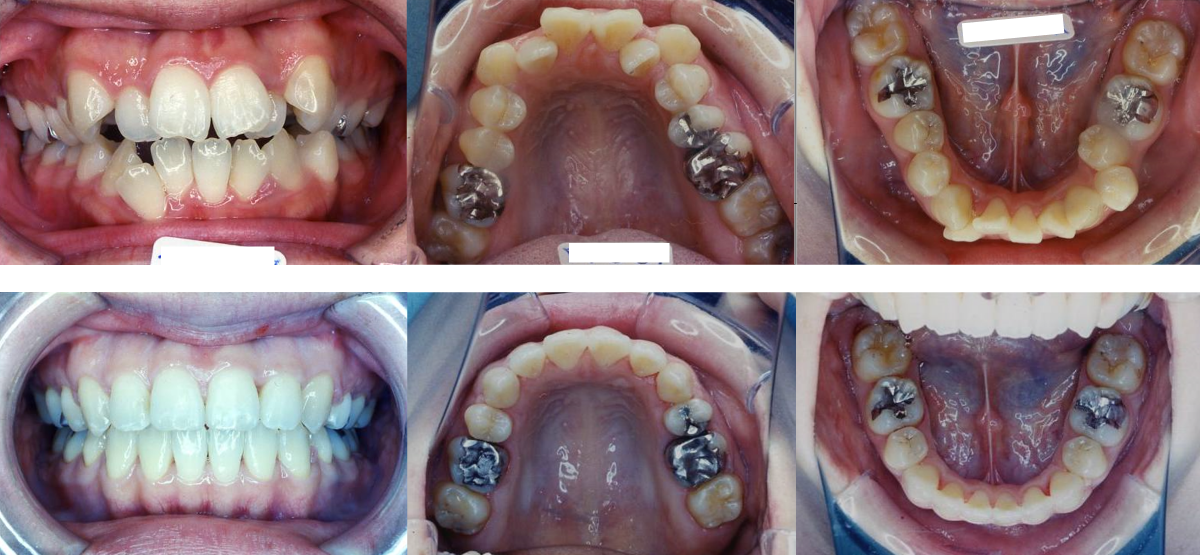

②叢生(でこぼこ)の矯正治療例(30代女性・治療期間2年2か月)

| 年齢・性別 | 30代女性 |

| 治療期間 | 2年2か月 |

| 抜歯 | 上2本、下2本(小臼歯) |

| 治療費 | 100万円(調整費、保定費まで含む総額制) |

| 備考 | 裏側矯正 |

| リスク・副作用 | 痛み・治療後の後戻り・歯根吸収・歯髄壊死・歯肉退縮 |